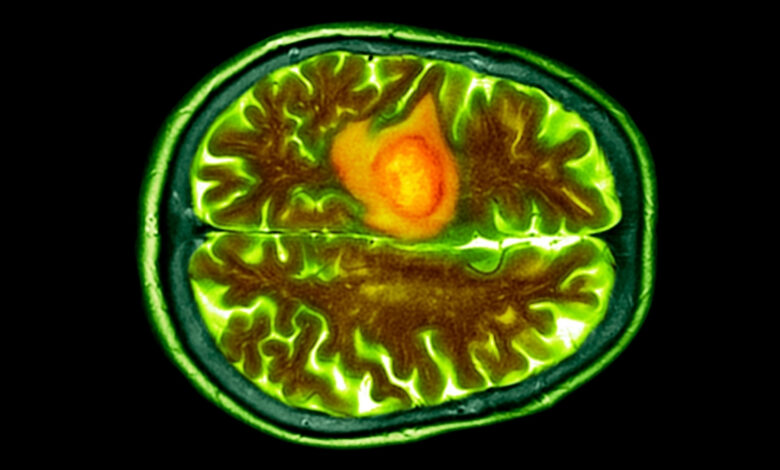

به گزارش سیناپرس، یکی از مرگبارترین انواع سرطان مغز، گلیوبلاستوما (Glioblastoma) نام دارد که متاسفانه شایعترین سرطان بدخیم مغز بوده و تنها ۶٫۹ درصد بیماران بیش از پنج سال پس از تشخیص زنده میمانند.

به گفته محققان، سرطان گلیوبلاستوما بسیار مهاجم بوده و در مراحل اولیه بهسختی تشخیص داده میشود و متاسفانه سیستم ایمنی بدن را فلج میکند. به همین دلیل درمانهای معمولی سرطان تقریباً در برابر آن بیاثرند. این تومور در مغز یا دیگر نقاط حساس سیستم عصبی مرکزی رشد کرده و به همین دلیل دسترسی مستقیم به آن بسیار دشوار و خطرناک است. این نوع سرطان همچنین با ایجاد تورم، فشار آوردن به بافتهای سالم اطراف و دزدیدن خون آنها، عملکرد مغز را بهسرعت مختل میکند.